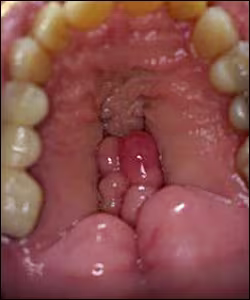

The torus palatinus is the most common atypical finding in the hard palate. These tori may range in size from very small to very large. They present as single or multilobular masses (Figure 31) and usually have a smooth surface texture. Often the larger tori will have traumatic ulcers or other traumatic lesions on their surfaces.

Figure 31. Extreme example of a multilobulated torus palatinus.

Tori are not usually considered a problem unless prosthetic appliances are being considered. Tori also make it difficult to expose intraoral radiographic films. Pathologic findings include: